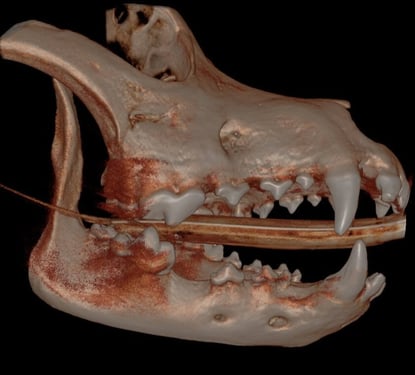

CT Imaging showed:

T/NV (non vital tooth) 204.

Missing 408 and 311, 411.

Beginning RR (root resorption) to lower rostral premolars - a common finding for dogs of this age and size

Below: 3D Overview before procedure: (left and right)